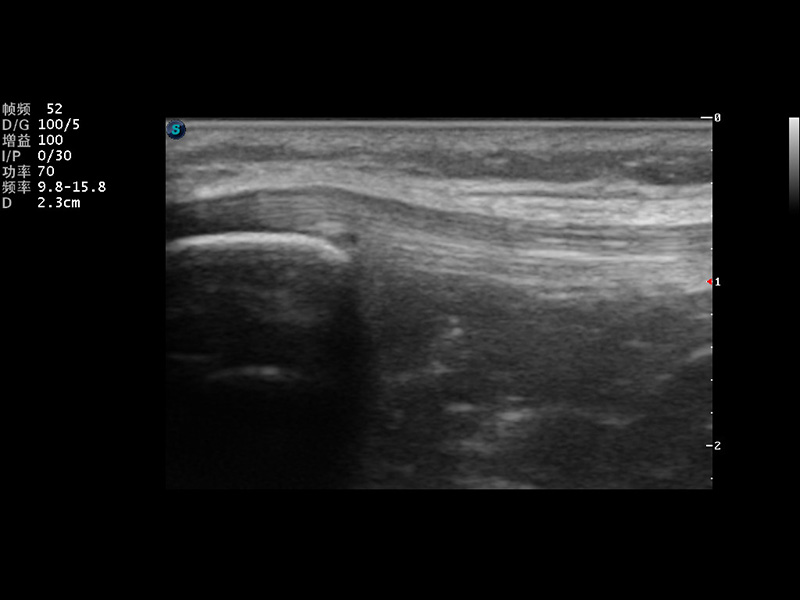

S9便携式彩色多普勒超声诊断仪是云顶集团官网研发的高端便携彩超设备,外观设计新颖、产品性能卓越。S9在便携超声领域采用了突破传统的触摸屏交互设计,并以先进的软件硬件技术和设计理念,为您带来清晰的图像质量、稳定的工作性能和便捷的操作体验。

成像技术